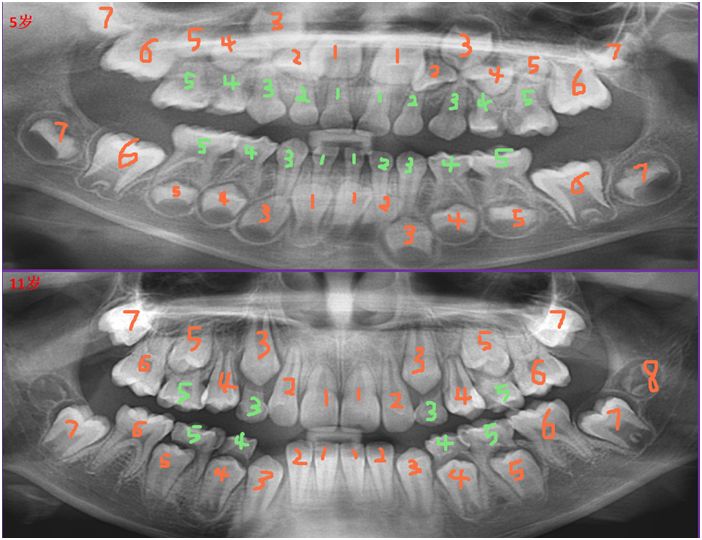

(上图为5岁和11岁小孩口内X线片的对比:绿色的为乳牙,橘红色的为恒牙,数字6为六龄齿)